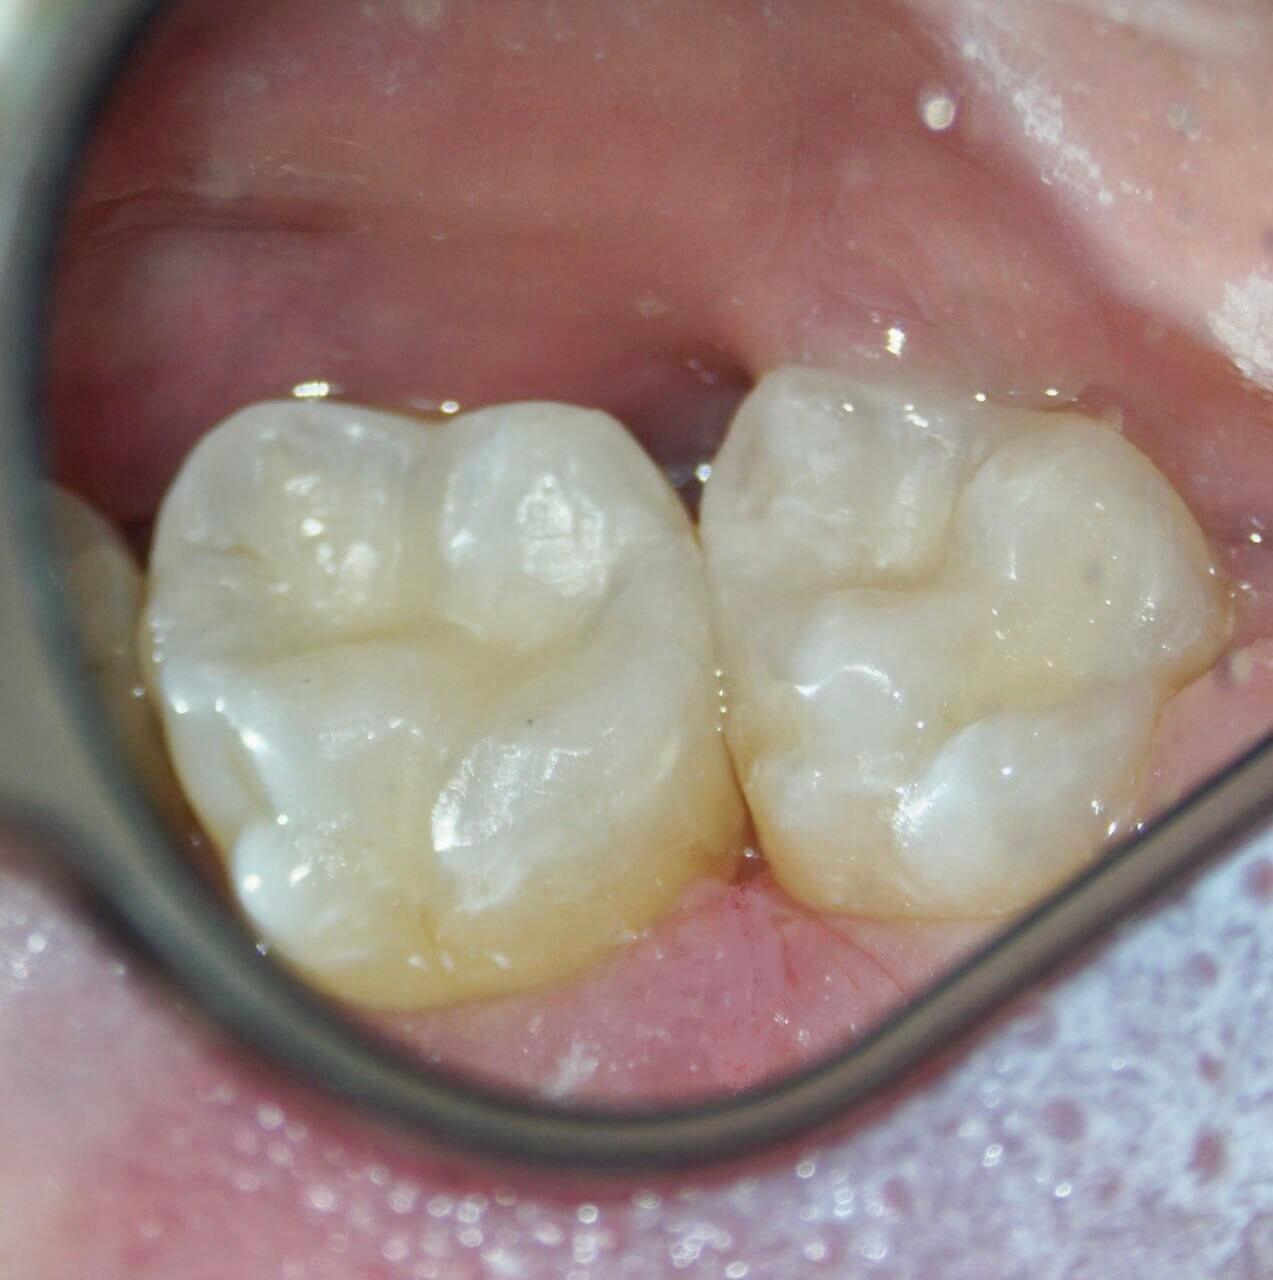

Итог: лечение кариеса, восстановление. Десна займёт своё физиологическое положение через пару часов, и полностью восстановится через неделю при хорошей гигиене.